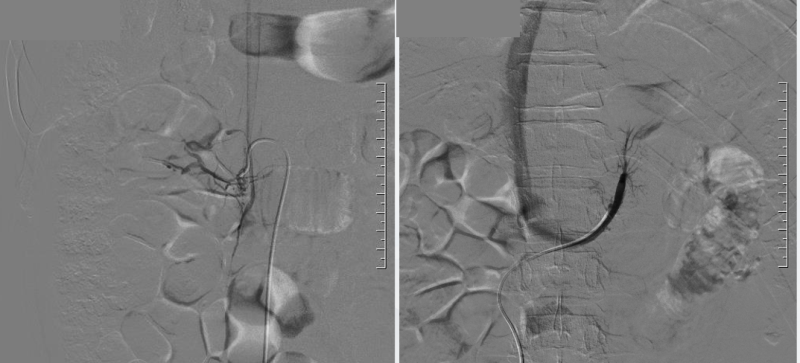

为明确诊断,高血压科立即启动精准检查方案。初步检查显示,王先生肾上腺左侧腺瘤,醛固酮定量(立) 36.152ng/dL,肾素定量(立) 0.919ng/L,醛固酮/肾素(立) 39.338,远超正常阈值,经盐水符负荷实验确诊原发性醛固酮增多症。要确定醛固酮的异常分泌来源,肾上腺静脉取血(AVS)是“金标准”。医院介入科刘要先主任、韩冰医生团队接手此项关键检查,在局部麻醉下,通过微创技术穿刺股静脉,将导管精准送入双侧肾上腺静脉,抽取血液样本检测醛固酮水平。结果明确为“左侧肾上腺优势分泌”——这意味着左侧肾上腺存在异常腺瘤,正是导致血压升高和低钾的“元凶”。